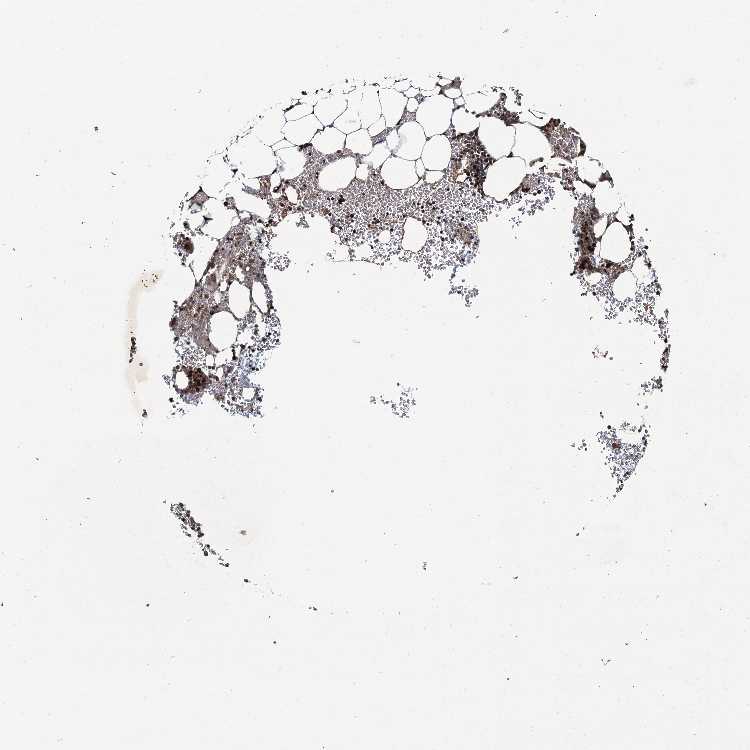

BONE MARROW - Antibody stainingi

Antibody staining in the annotated cell types in the current human tissue is reported as not detected, low, medium, or high, based on conventional immunohistochemistry profiling in selected tissues. This score is based on the combination of the staining intensity and fraction of stained cells.

Each image is clickable and will lead to virtual microscopy that enables deeper exploration of all samples and also displays staining intensity scores, fraction scores and subcellular localization as well as patient and tissue information for each sample.

Antibody HPA041775

Hematopoietic cells Medium